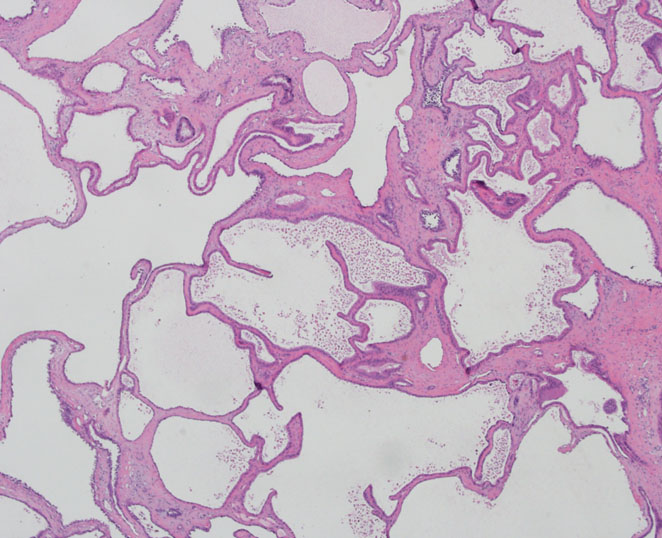

Consensus grade: Tubulocystic RCC

| Pathologist 1 | Tubulocystic RCC | Typical | |

| Pathologist 3 | Tubulocystic RCC | Typical | |

| Pathologist 7 | Tubulocystic RCC | Typical | |

| Pathologist 8 | Tubulocystic RCC | Typical | |

| Pathologist 11 | Tubulocystic RCC | Typical | |

| Pathologist 12 | Tubulocystic RCC | Typical | |

| Pathologist 13 | Tubulocystic RCC | Typical | |

| Pathologist 14 | Tubulocystic RCC | Typical | |